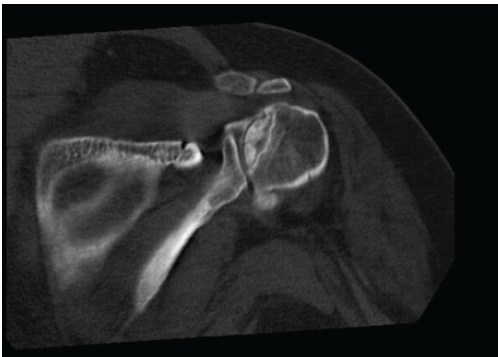

A 37-year-old woman with a body mass index (BMI) >40 presented to our orthopedic clinic in April 2024 for shoulder and hip pain. She was a non-smoker and denied drug and alcohol use. She reported first noticing joint pain in November 2023, approximately 2 years and 4 months after a severe COVID-19 infection in July 2021. Her COVID-19 disease process was complicated by asystole, acute kidney injury (AKI), shock liver, and acute encephalopathy. In the hospital, her AHRF was managed with intubation and a cumulative dose of 1640 mg of steroids. Before COVID-19, her past medical history included Class III obesity, prediabetes, polycystic ovarian syndrome, hypertriglyceridemia, hypertension, chronic bronchitis, anxiety, and depression. She was taking no chronic steroids; her bronchitis was managed with albuterol and montelukast. Initially, the patient’s COVID-19 infection was diagnosed at the pharmacy, but she later presented to the emergency department for respiratory distress, where 2 days of 20 mg of prednisone were prescribed. Due to worsening symptoms, the patient was then hospitalized for AHRF and received 40 mg of methylprednisolone twice per day. After succinylcholine administration for intubation, she went asystolic and needed cardiopulmonary resuscitation. After reanimation, transesophageal echocardiography showed a transient cardiomyopathy with reduced ejection fraction at 45–50%. Laboratory values showed elevated D-dimer levels, peaking at 17.73 mg/L (normal <0.5 mg/L), and elevated inflammatory markers, specifically an interleukin-6 of 56.54 pg/mL (normal <7.01 pg/mL), C-reactive protein of 279.30 mg/L (normal < 5 mg/L), and procalcitonin of 0.11 ng/mL (normal <0.1 ng/mL). During hospitalization, creatinine levels increased, indicating AKI; her alanine transaminase rose to 1318 U/L, indicating shock liver. She was also diagnosed with acute encephalopathy, evidenced by abrupt neurological changes, disorientation, reduced concentration, and slow speech. Overall, she spent 27 days in the hospital and received 1640 mg of steroids. After discharge, she received rehabilitative care at a nursing home. In November 2023, approximately 2 years and 4 months after being admitted for COVID-19, she was referred to rheumatology by her primary care physician for hip, knee, and shoulder joint pain of unknown etiology. With a history of metabolic encephalopathy overlying preexisting anxiety and depression, radiographic imaging without osseous findings, a positive antinuclear antibody, and no other rheumatological biomarkers, the rheumatologist diagnosed her with fibromyalgia. In March 2024, she was referred to a bariatric arthroplasty clinic for worsening hip pain and new-onset numbness and tingling. At the clinic visit, she had a positive Stinchfield test, and she reported a previous magnetic resonance imaging (MRI) of her left knee that had shown evidence for bone infarcts. Radiographic imaging of the hips was performed, showing bilateral AVN with collapse of the left femoral head. The patient was told that total joint arthroplasty was not an option at that time due to her elevated BMI and inflammatory markers. In April 2024, her primary care physician referred her to our orthopedic clinic for joint aspiration and intra-articular steroid injections. At that time, she was barely able to walk and also complained of increasing shoulder pain. Physical examination showed bilateral pain on palpation over the greater trochanters and the biceps tendons; she had a positive apprehension test and reduced shoulder range of motion. In April 2024, bilateral hip fluid aspiration with intra-articular steroid injections was performed. No marked effusions were found, and fluid cultures failed to show growth. Pain relief from the steroid injection lasted 2 weeks. Being a poor surgical candidate, in June 2024, bilateral femoral head core decompressive surgery was performed to try to delay total hip arthroplasty (THA) by improving interosseous blood flow. Due to continued pain, in August 2024, the shoulders and hips were imaged. Radiographs of the hips indicated no improvement of AVN despite decompressive surgery; there was Ficat-Arlet stage IV AVN bilaterally with crescentic sclerosis and bilateral femoral head collapse with greater collapse of the left femoral head (Fig. 1). Bilateral computed tomography angiography of the shoulders showed AVN affecting 75% of the surface areas in the humeral heads bilaterally, bilateral tendinosis of supraspinatus and infraspinatus muscles, and some degenerative changes in the long head of the right biceps (Fig. 2 and 3).

Figure 3: Computed tomography image of the right shoulder of a 37-year-old woman with multifocal osteonecrosis. The image was obtained on August 21, 2024. At present, no interventions have been performed on the avascular necrosis in the patient’s shoulders.